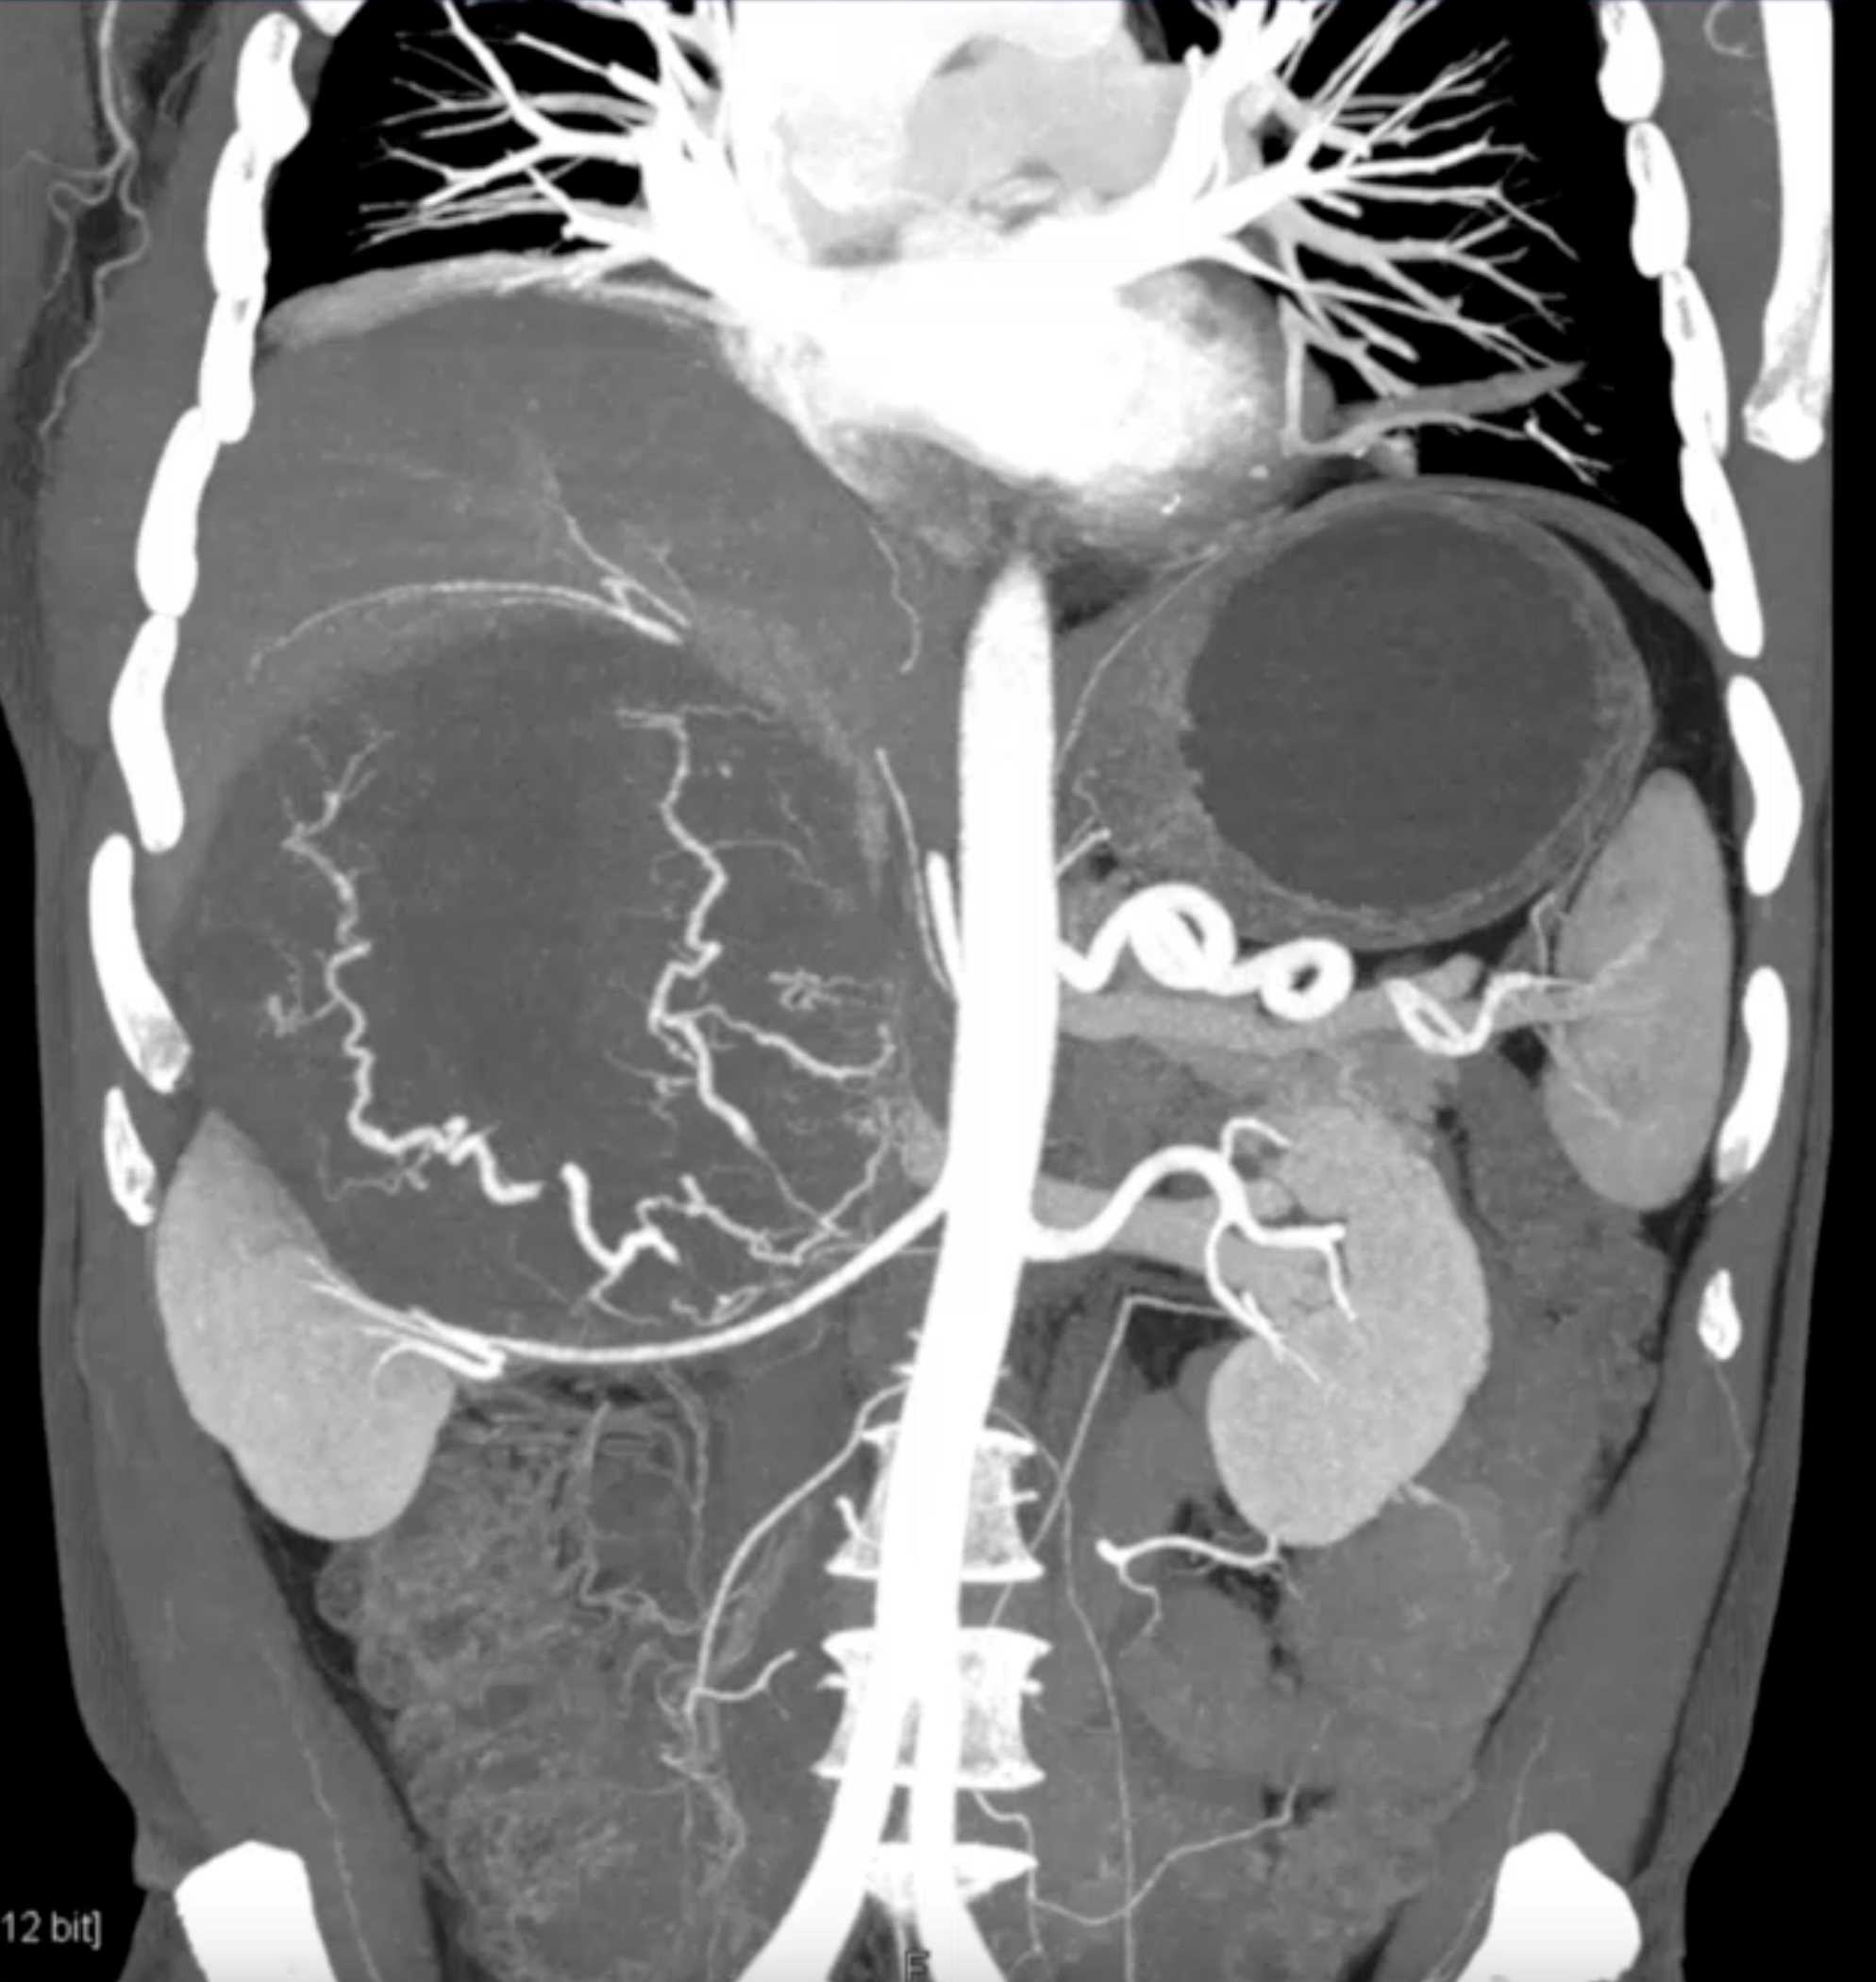

Left Adrenal Metastases from Renal Cell Carcinoma